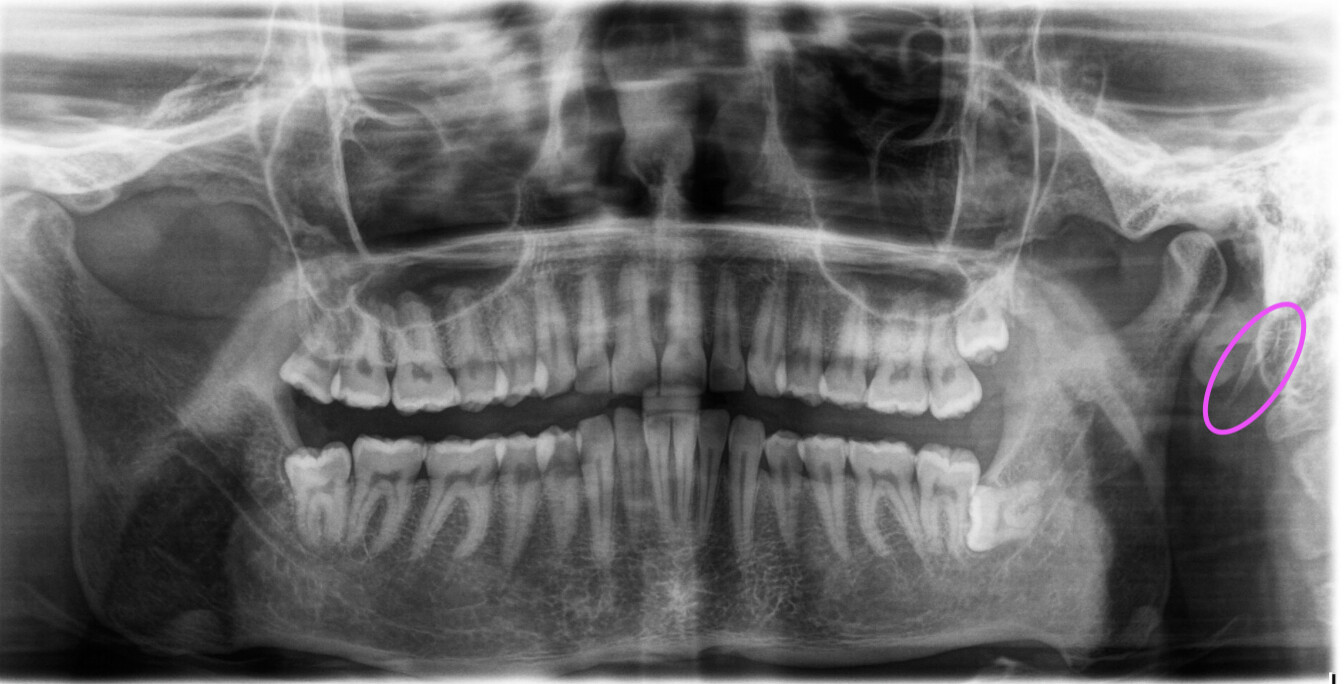

For some context, I’m 28M. I have not been diagnosed with Eagle’s, though I do expect that I either have it or some adjacent disorder. My life has been on a consistent downswing for the last year+. In October of 2024, I started having sporadic pulsate tinnitus and dizziness in my right ear. I wrote it off as nothing, potentially stress related, but my symptoms progressed. Around November I started having icepick headaches, head pressure, dizziness, and brain fog, as well as a feeling of fullness on the left side of my neck. In December I turned my head while speaking to my partner and felt a rubberband snap (which I know is a symptom that many report here) in my upper left neck, right below my jaw, instantly followed by dizziness and confusion. This rattled me - I feared I was having a stroke or TIA - and I ended up in the ER the next day. Everything came back normal. I followed up with several ENTs who sent me for a head MRI, a head MRA and MRV, and a contrasted 2D neck CT (I don’t have this on hand, nor do I have the images, as I have to pick up the disc from the physical location a state over, and I’ve done so several times but have ended up foolishly leaving the discs at doctor’s offices, but I am working on getting another copy which I plan to download). All of these tests sent me on alternative paths, never addressing my root symptoms: we found a malformation/ossification in my nose, likely due to me breaking my nose as a child, and I saw two ENT’s regarding this as one thought it looked portentously suspicious and wanted to operate on it, the other saying it was benign. I got two biopsies for enlarged submandibular lymph nodes, which are still enlarged to this day, all coming back negative. I’ve seen a neurologist, multiple rheumatologists, five ENTs, and a GP in the past year - none of which can locate what is wrong with me. I also saw a dental surgeon in May due to bony protrusions appearing on the roof of my mouth, and she advised that I should get an ENT to investigate the potential for Eagle’s syndrome. After weeks of searching I finally found one and provided him a copy of the 2D CT, and he said my styloids looked fine. No elaboration, no further thoughts on what could be causing my symptoms, and since then I’ve been lost on how to further pursue treatment or diagnosis. I’ve spent thousands of dollars on tests, and yet I’ve had difficulty finding a doctor who is willing to engage in a full dialogue or one who seems to really care if I live or die. All the while I feel pressure/tapping in my neck, which has become prickly and painful, I have severe brain fog and derealization, chronic nausea, eye pain/twitches, sharp temple pain, tingles running from my scalp to my upper back. Sometimes I feel a sort of wiry pressure running from my left shoulder all the way up to the back of my head. I also have a hard, constant lump behind my left ear which feels bony. I have trouble sleeping at night due to the discomfort in my neck. I can’t run, and stopped going to the gym for fear of worsening the structures in my neck. I want to be free of this, but most of all I want to know definitively what’s wrong with me.

I apologize for the venting/text dump. If anything here indicates some elongation of my styloid process, or evidence of calcification, I would love to know so that I can further pursue treatment. I made an appointment with Dr. David Kutler in NYC for next month, as I’ve read that he diagnosed someone here with Eagle’s, so maybe there is some hope on the horizon.